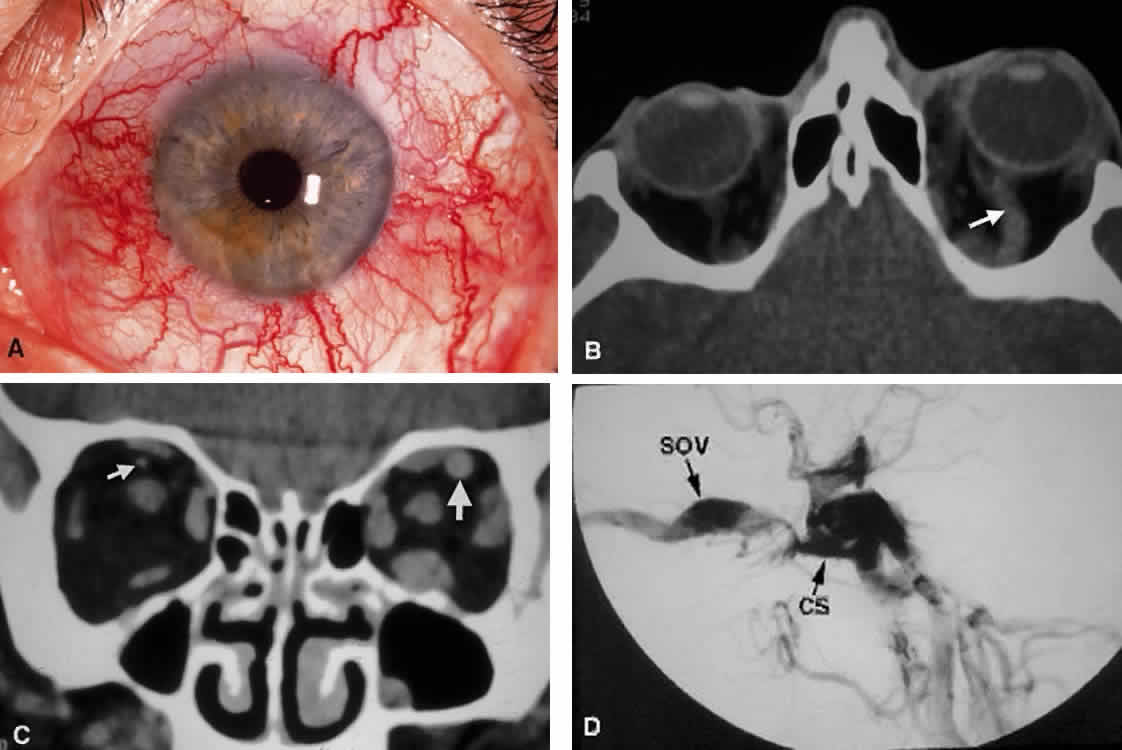

Second, the motor fibers to the EOMs usually enter the inner aspect of each muscle at the junction of the posterior one third and the anterior two thirds of the muscle's length. The exception is the nerve to the inferior oblique, which runs along the lateral aspect of the inferior rectus muscle to enter the inferior oblique muscle near the globe's equator (see Fig. 14). This nerve may be damaged with manipulation of inferior orbital soft tissue during repair of an orbital floor fracture. Because the parasympathetic fibers of the pupil also travel with the nerve to the inferior oblique at the orbital apex, any anterior traction may cause contusion to these more posterior fibers, resulting in a postoperative Adie's pupil.14 VASCULAR SUPPLY Arteries The tissues of the orbit and periorbital region derive their blood supply from two sources—the internal and external carotid arteries.15 Although the majority of orbital blood supply comes from the ICA, anastomoses with external carotid supply are numerous. The ICA enters the calvarium through the foramen lacerum, runs near the posterior clinoid process, and then makes a sharp turn to enter the CS with the abducens nerve (see Fig. 13). As already noted, within the CS the ICA has an S-shaped course called the carotid siphon. As the ICA exits the CS, it gives off its first major intracranial branch, the ophthalmic artery. Before giving off the ophthalmic artery, the ICA has several minor branches that supply the meninges, including the dura of the lateral wall of the CS. An abnormal communication between the arterial and venous supply of the CS results in either a carotid-cavernous fistula or a dural-sinus fistula (Fig. 18A). Because of the larger caliber of the ICA, a carotid-cavernous fistula is usually symptomatic secondary to a high flow state, possibly manifesting as orbital/ocular ischemia and increased intraocular pressure. This type of fistula is most commonly encountered in younger patients after blunt trauma and may require invasive neuroradiologic treatment (Fig. 18B). Conversely, a dural-sinus fistula is typically a low-flow state because the abnormal communication forms between the small-caliber dural arterial feeders of the lateral CS wall and the venous plexus of the CS. Such fistulas are usually seen in older individuals as a spontaneous event. Depending on the severity of symptoms, most dural sinus fistulas are simply followed by observation because of the high rate of spontaneous closure. The ophthalmic artery enters the optic canal inferolateral to the optic nerve, carrying with it a sympathetic plexus from the ICA. The intraorbital course of the ophthalmic artery is highly variable. In about 83% of cases, the artery crosses over the optic canal from lateral to medial and continues to travel superomedially in the orbit to its terminal branches. While still within the orbit, the ophthalmic artery gives off several branches.16 These are most easily subdivided into three groups: ocular, muscular, and extraorbital (Table 12, Fig. 19).